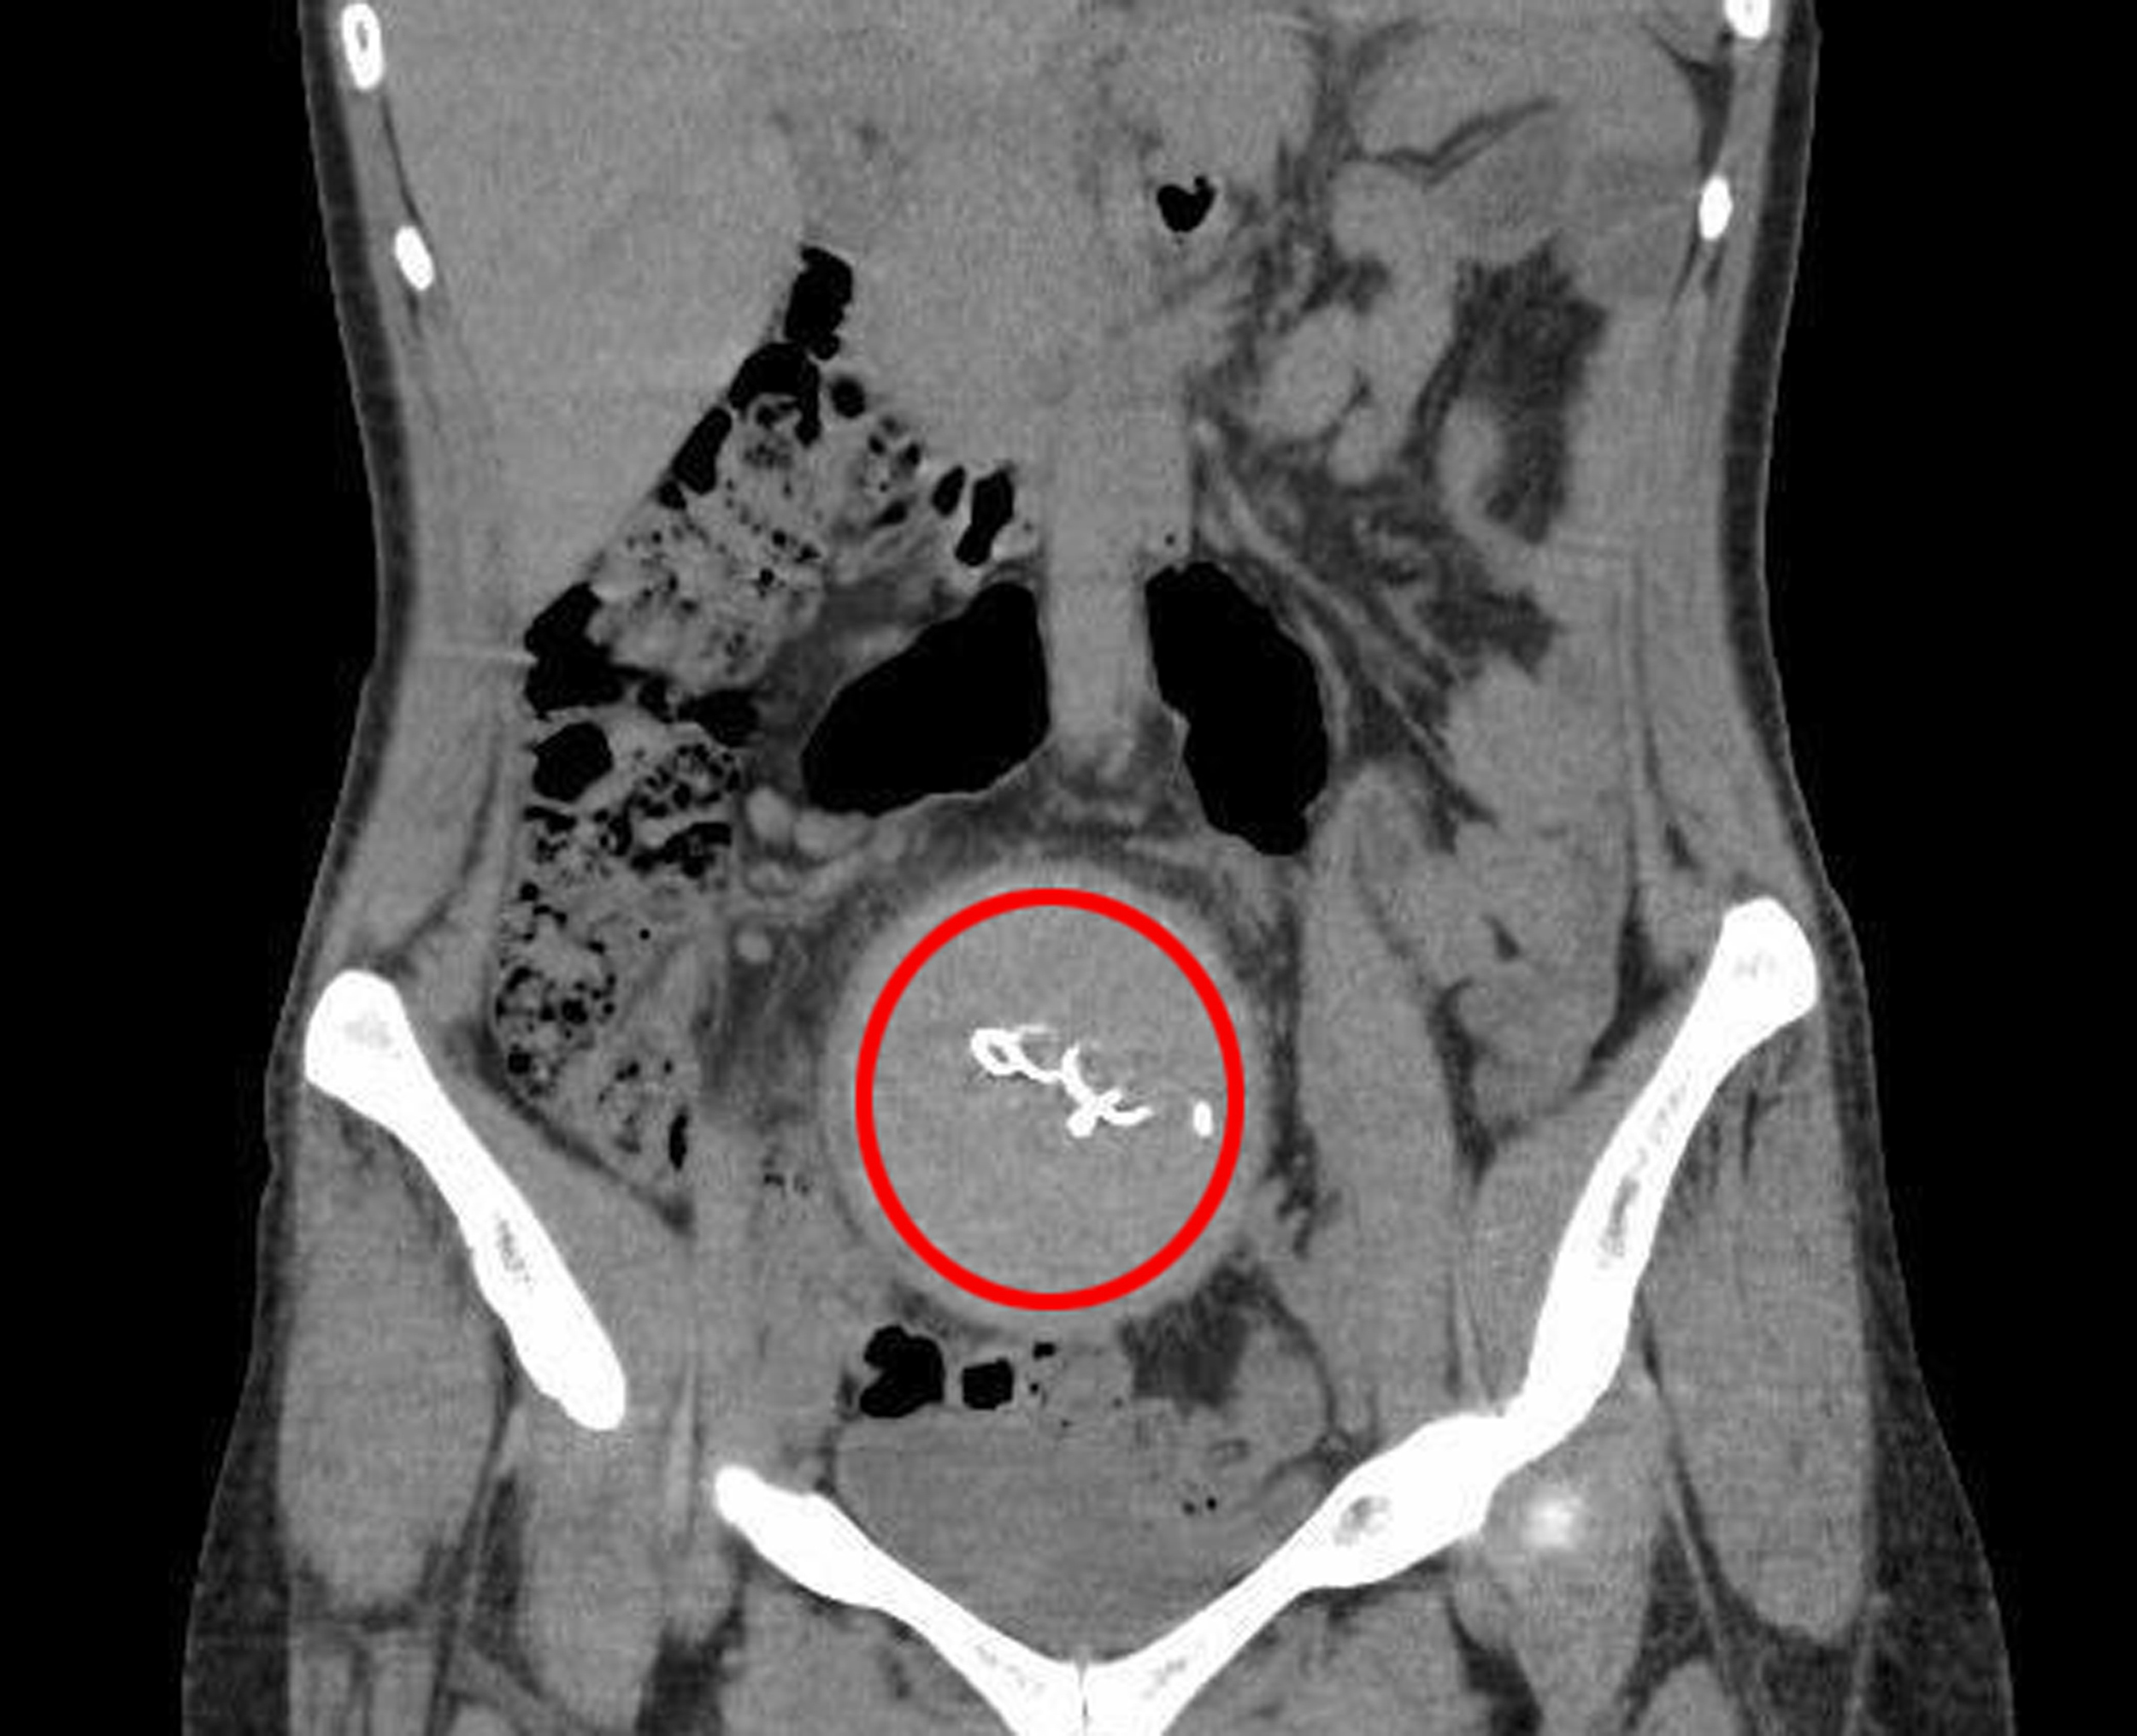

Burada yapılan kontrolde, doktor acil tomografi çektirmesini istedi. 2023 yılının Ağustos ayında çekilen tomografide, Y.S.'nin vücudunda doğum sonrası unutulan sargı bezi görüldü. Şoke olan Y.S., 2 yıldır yaşadığı ağrılara ihmalin sebep olduğunu öğrendi. Y.S.'nin karnında unutulan yaklaşık 30 santimetre uzunluğundaki gazlı bez ameliyatla alındı. Y.S., hastane ve süreç içerisinde ihmali bulunan doktorlar hakkında savcılığa suç duyurusunda bulundu.